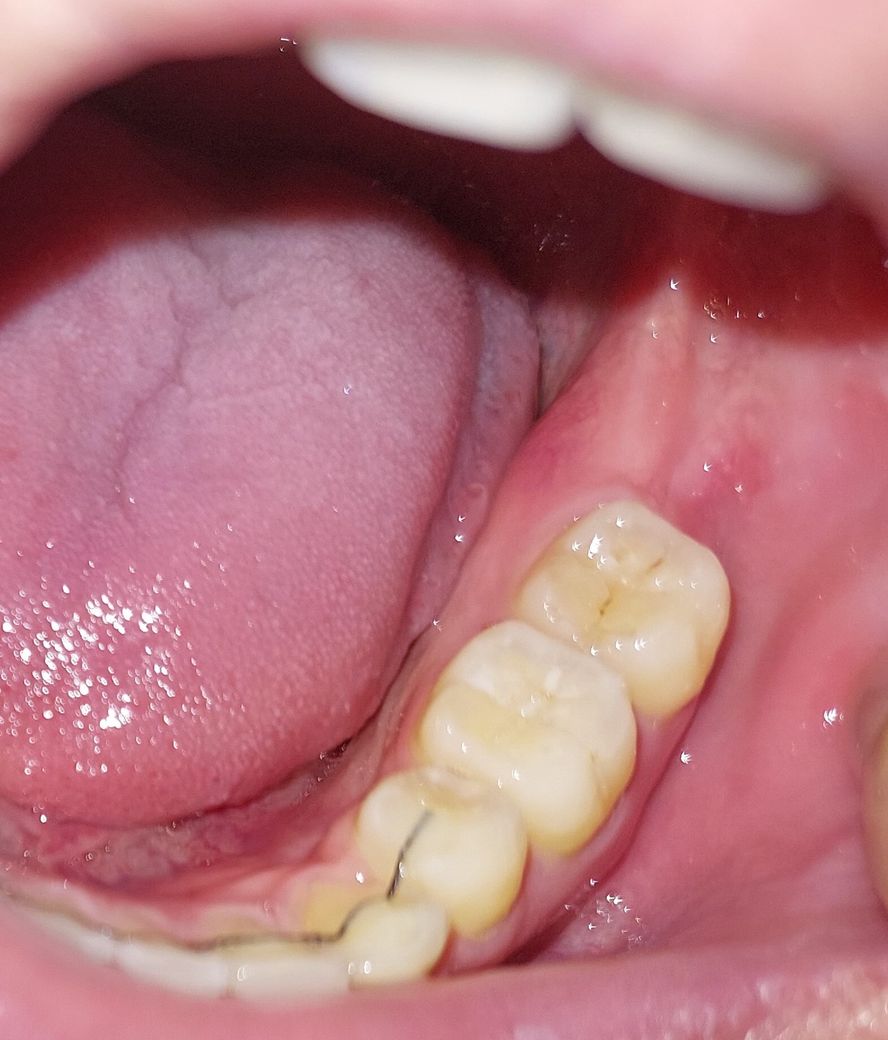

병원가서 진료봤는데 첫사진이 병원에서 찍어준 사진이고 충치 치료해야한다고 하는데요

근데 제가 집에 와서 카메라로 찍으니깐 오른쪽 어금니(사진상 왼쪽)에 있는 큰 검은색부분이 안보여서 이거 그냥 음식물 낀거같은데 이정도면 충치 치료할필요 전혀 없는 수준이죠?

• 1번 째 사진